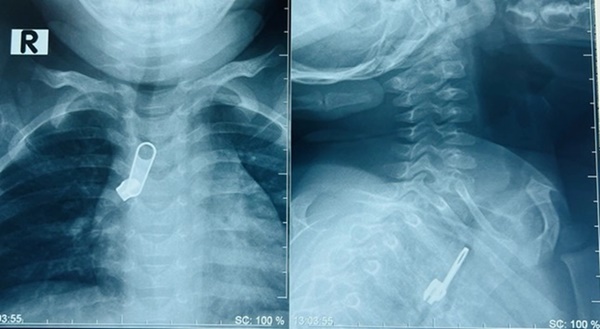

Chiếc móc chìa khóa lọt vào đường thở khiến bệnh nhi phải nhập viện

Tại đây, qua thăm khám và chụp X-quang bác sĩ phát hiện dị vật nằm phía trước cột sống ngực lệch phải, ngang mức đốt sống T3-T5 của bé.

Bệnh nhi nhanh chóng được chuyển đến khoa Tai Mũi Họng và chỉ định nội soi gắp dị vật. Sau khi gây mê, bằng thiết bị nội soi chuyên dụng cho trẻ, BS Lý Phạm Hoàng Vinh cùng ê kíp đã gắp thành công móc khóa kéo trong phế quản bên phải của bệnh nhi ra ngoài.